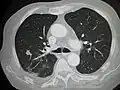

Initially, nearby lymph nodes are struck early.[9] The lungs, liver, brain, and bones are the most common metastasis locations from solid tumors.[9]

- Lung metastasis: cough, hemoptysis and dyspnea[9] (shortness of breath)

Metastatic tumors are very common in the late stages of cancer. The spread of metastasis may occur via the blood or the lymphatics or through both routes. The most common sites of metastases are the lungs, liver, brain, and the bones.[10]